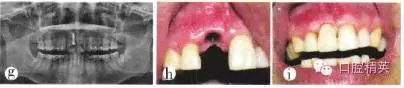

(3)種植修復(fù):拔牙后3個月行種植修復(fù)。全景片顯示牙槽骨高度及種植空間基本正常(圖1e)。植入1顆3.3 mm×10 mm瑞士ITI種植體;由于唇側(cè)根尖區(qū)骨質(zhì)破壞,致根部種植體暴露約2 mm,取舌側(cè)骨板碎塊充填,嚴(yán)密縫合。術(shù)后x線全景片顯示植體位置、高度等均較理想(圖1f)。種植術(shù)后3個月行上部修復(fù),全景片顯示植體周圍骨質(zhì)致密,骨高度尚可(圖1g)。種植體愈合良好、穩(wěn)固,袖口成形較好(圖1h)。完成種植義齒上部修復(fù)(圖1i)。隨訪:種植修復(fù)完成后患者對咀嚼效率和美觀效果均較滿意。現(xiàn)已完成種植修復(fù)3年余,修復(fù)體穩(wěn)固,咀嚼效率高,牙齦形態(tài)良好,美觀效果較好。

圖1e種植術(shù)前全景片;f種植術(shù)后全景片;g種植上部修復(fù)前全景片;h牙齦袖口形態(tài);i種植修復(fù)完成